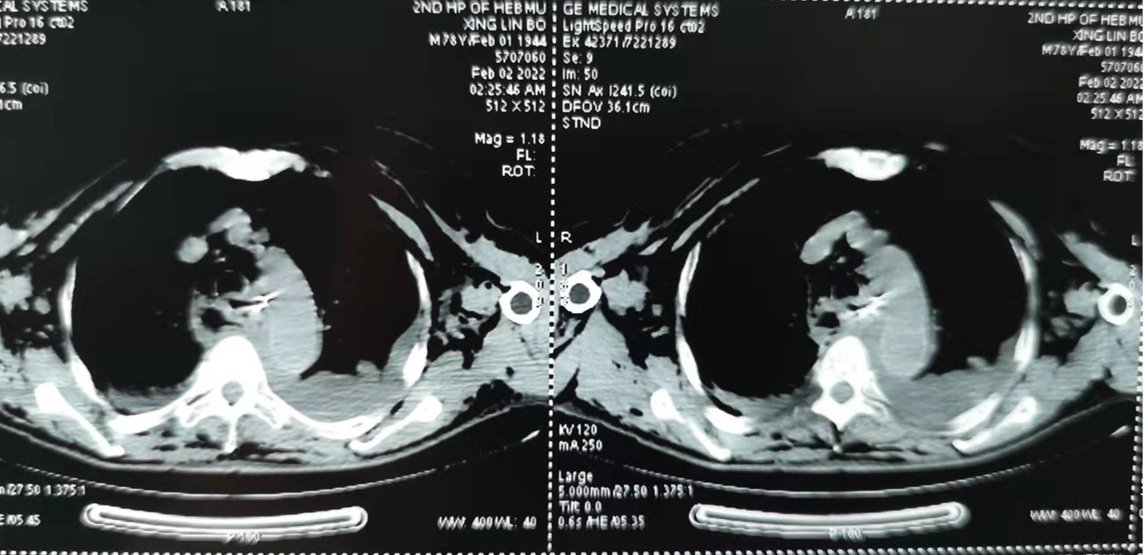

患者是一位77岁的男性,就在刚刚过去的除夕,进食阖家团圆的年夜饭时,不小心吞食一颗义齿,当即感觉吞咽困难,随后出现胸部疼痛。于是大年初一到衡水市某医院就诊,查电子鼻咽喉镜,发现左侧梨状窝外侧壁隆起,左侧披裂粘膜肿胀。胸部CT显示食管上段异物。食管镜检查显示距门齿20cm处见异物,左上端可见金属钩,周围粘膜肿胀、糜烂,可见少许出血。用异物钳钳加金属钩至食管入口处,不能取出异物,考虑异物下端金属钩嵌顿于粘膜内,于是大年初二就诊于我院。

于是消化内科联系胸外科、麻醉科、手术室进行多学科会诊。由于患者高龄、且误吞义齿时间较长,已经出现食管穿孔、纵隔气肿、纵隔感染、皮下气肿、急性呼吸窘迫综合征、右侧气胸、双侧胸腔积液,患者的一般情况较差及以上众多合并症,病情复杂,治疗风险高。但内镜下治疗已经尝试2次,且第二次患者出现血氧饱和度明显下降,生命体征不平稳,不宜再次行内镜诊疗。综合考虑后,本着彻底为患者解决问题的宗旨,制定了开胸取出异物的治疗方案。